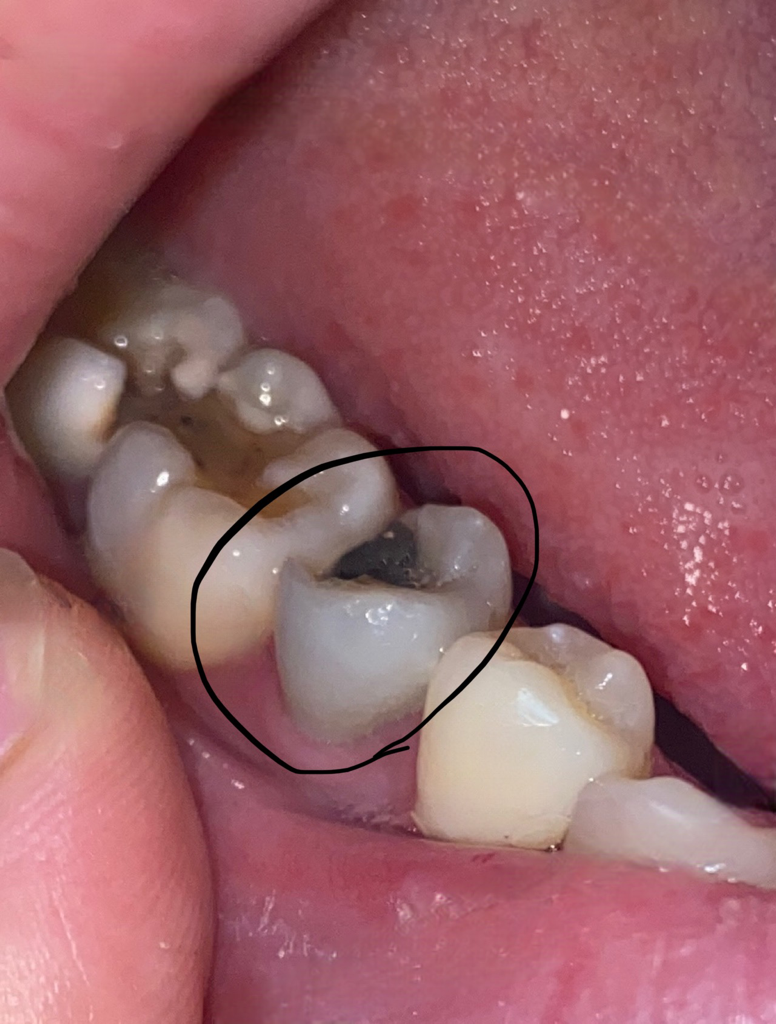

제가 양쪽 어금니쪽이 다 썩어있었어서 1년전에 더 통증이 심했던 왼쪽은 치아색으로 씌우는 치료받고 오른쪽은 오래전에 떼우는것만 했던거 같은데 음식을 오른쪽으로 씹거나 차가운 물 닿거나하면 시리고 아파서 왼쪽으로만 씹고 양치도 따뜻한 물로만 하면서 그렇게 1년이 지났는데 오늘 치실하다가 이물질 같이 보여서 저 안 부분을 건드렸다가 맨끝 치아 일부가 저렇게 파였는데 떼운게 떨어진건가요??!? (빼냈을때 단단하기보단 하얀색 이물질 같은것만 나왔는데 빼고나서 만졌을때에 원래 통증은 없었는데 아파요 ㅠ) 그리고 끝에서 2번째 치아 부분은 파이진 않았는데 사진보니 변색된건가요? 이상해보여서 어떤 상태인지 알 수 있을까요 ㅠ

저 검은색으로 떼운 부분 (검색해보니 아말감?이라고하네요) 저 치아만 치아자체가 약간 검푸르게? 변했는데 저거때문인건가요 ㅠㅠ?? 한지 3-4년정도 됐어요 저 부분은 통증은 하나도 없어서 충치는 아닌거 같은데 ㅠㅠ

사진으로만 봤을 경우에는 충전을 했던 부위가 탈락이 되면서 내부에서 충치가 생긴 것으로 보입니다. 추가 있는 부위는 충치를 제거하고 치고용 재료로 다시 충전을 해주거나 보철치료가 필요할 수 있습니다. 자세한 확인을 위해서 치과에서 진료를 받아보세요.

떼운 충친재가 일부 떨어져 나간것으로 보이며, 이경우 재치료가 필요로 되기에 빠른 시일내에 치과에 방문하여 치료를 받기 권합니다.